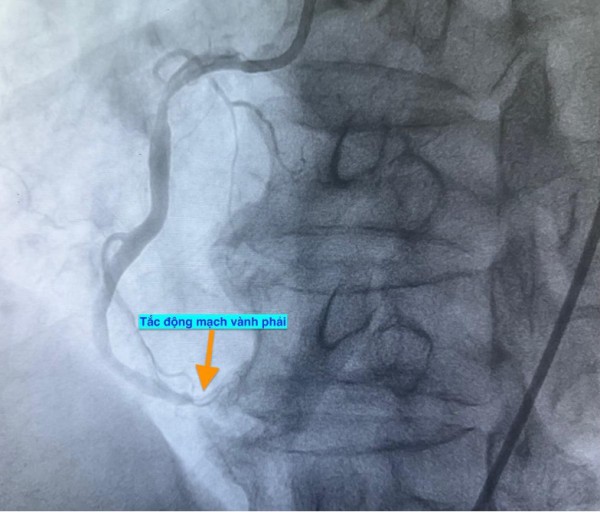

Trường hợp thứ nhất, lúc 0 giờ 34 phút ngày 14.11, nam bệnh nhân 51 tuổi vào bệnh viện vì mệt và khó thở. Chụp mạch vành phát hiện bệnh nhân bị tắc hoàn toàn động mạch vành phải.

Hình ảnh chụp mạch vành cho thấy các bệnh nhân bị tắc mạch máu tim (do mảng xơ vữa, huyết khối) dẫn đến tình trạng thiếu máu cục bộ và nhồi máu cơ tim cấp

ẢNH: BV